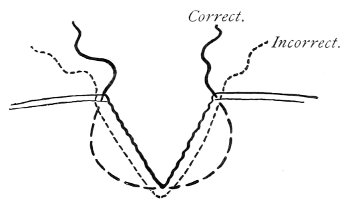

If this tear is detected after labor, it should be closed by the immediate operation. A slight tear involving chiefly the cutaneous aspect of the perineum should be closed by three or four sutures introduced from the outside, as in Fig. 33. The needle should be introduced about a quarter of an inch from the edge of the wound. It should not be passed parallel with the plane of the lacerated surface, but should be swept outward and then inward toward the 68 angle at the bottom of the tear (Fig. 34). It may either emerge at the angle and be re-introduced, or it may be passed directly through to the skin-margin on the opposite side of the wound. If the suture is passed in this way, there will be perfect apposition throughout the whole surface of laceration. If the sutures are improperly passed, there may result only apposition of the skin-edges.

Fig. 34.—Diagram representing the correct and the incorrect method of passing the suture for closure of slight perineal laceration.